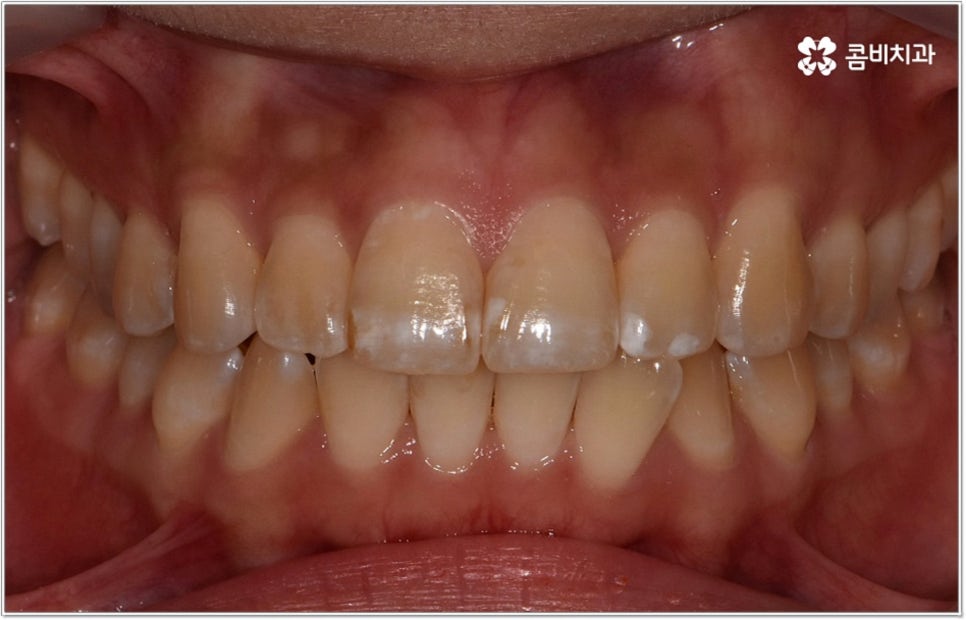

누군가와 이야기하고 있을 때 상대방의 입 속으로 언뜻언뜻 보이는 치아가 희고 고르면 깔끔하게 자기 관리를 잘 하는 사람이라는 인상을 주기 때문에 처음 보는 사이라도 호감도가 올라가는 경험을 해 보신 적이 있으실 거예요. 반대로 자신의 치아가 삐뚤빼뚤하다면 대인관계에서 조금 위축이 되기도 하고 웃을 때마다 자기도 모르게 치아를 손으로 가리는 습관을 갖게 될 수도 있는데요. 이렇게 치아 배열이 심미적, 심리적으로 주는 영향이 상당하기 때문에 아름다운 치아를 드러내며 환하게 웃는 미소에 대한 로망을 가지고 있는 분들이 많이 있습니다.

게다가 치아는 우리가 매일 음식을 먹을 때 이를 잘게 잘라주는 역할, 그리고 말을 할 때 발음을 정확하게 해 주는 역할 등 일상 생활 속에서 꼭 필요한 기능들을 하고 있는데요. 그렇기 때문에 만약 치아 배열이 고르지 못하다면 음식물을 제대로 씹기 어려워져서 소화 불량 및 영양 불균형을 초래하여 장기적으로 전신 건강에 좋지 않은 영향을 줄 수도 있고 발음이 새고 불명확해 질 수도 있으므로 기능적인 측면에서 봐도 치열에 대해 관심을 기울이실 필요가 있어요. 더욱이 교합이 맞지 않은 채로 계속 씹는 과정을 반복하게 되면 턱관절 통증을 느끼게 되거나 안면비대칭까지 이어질 수 있고 고르지 못한 치아 사이로 음식물이 자주 끼어 충치, 치주염 등의 구강 질환이 발생할 가능성 역시 높아지기 때문에 치열이 삐뚤어져 있거나 상하악 교합이 정상적이지 않다면 치아교정 치료를 통해 이를 바로잡아 주는 것이 좋을 거예요.

요즘은 관련 치의학 기술이 많이 발달하여 환자분들께서 치아 교정을 할 때 느낄 수 있는 여러 가지 불편들을 크게 줄여 주고 있지만 그럼에도 불구하고 여전히 통증에 대한 걱정이나 비교적 오래 걸리는 기간, 비용적인 부담 등으로 인해서 치아 교정이 망설여지는 분들이 있을 거예요. 또한 치아 교정을 하면 꼭 발치를 해야 하는가에 대해서도 많이들 문의를 주시고 있는데요. 물론 치아를 뽑는 것에 대한 걱정은 남녀노소 불문하고 누구나 가질 수 있는 것이지만 교정을 한다고 해서 반드시 발치를 해야 하는 것은 아니며 환자분들의 상황에 맞게 비발치치아교정 치료를 진행할 수도 있기 때문에 이에 대해서 꼼꼼하게 살펴보시면 막연한 두려움을 줄일 수 있을 거라 생각하고 있습니다.